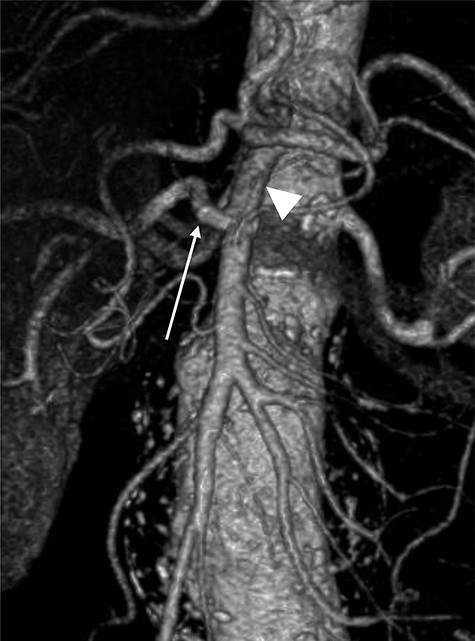

Terumo Aortic Anaconda three-vessel fenestrated and bilateral iliac branched graft was used for repair and was deployed in perirenal position with stents to the SMA and both renal arteries. Surgical arterial access was via left axillary artery (LAA) and percutaneous access was ultrasound-guided via common femoral arteries (CFA) bilaterally. Cannulation of left renal artery (V12 5 × 22 mm) and SMA (V12 9 × 32 mm) was via CFA and right renal artery (V12 5 × 22 mm) was through LAA. There was intra-operative difficulty in SMA cannulation, which was eventually cannulated after repositioning of graft (Fig. 3). Final intra-operative angiogram showed patent renal arteries bilaterally, SMA and common iliac arteries bilaterally (Fig. 4). Post-operatively, he was transferred to surgical high dependency unit (HDU). Three days post FEVAR, he developed abdominal pain, haematemesis and melaena with significantly raised inflammatory markers. CT mesenteric angiogram showed an ischaemic small bowel segment. A necrotic gallbladder was found incidentally during laparotomy, which required cholecystectomy after 20 cm segment of small bowel had been resected and decision was made to not anastomose the small bowel due to the intra-operative findings. A relook laparotomy was performed for small bowel anastomosis and drainage of bile collection found in the gallbladder fossa. Histology results later confirmed infarcted gallbladder with extensive acute inflammation as well as congested, ischaemic and focally infarcted small bowel segment with peritonitis.

Mid-implantation angiogram showing both renal stents deployed (arrowheads) and SMA cannulated (arrow).